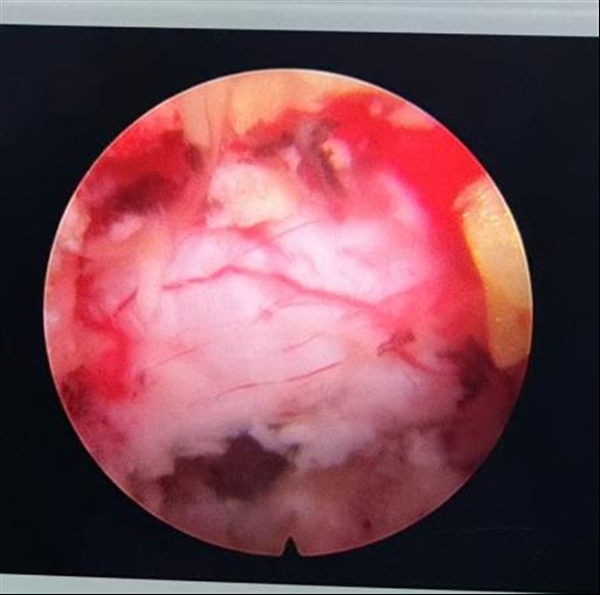

历经近 2 小时高度专注的操作,手术进展顺利。张世民主任在微创视野下,灵活运用骨刀、磨钻、环锯等多种微创器械,对患者严重增生的骨性结构进行精细减压。团队在严格保护神经根的前提下,自背侧逐步向深部推进,整块切除增生肥厚的黄韧带,可见被压迫的神经根褶皱变形。随后继续进行腹侧减压,精准去除突出物,见神经根搏动良好、血供恢复、减压彻底,让受困的神经根重新获得自由空间。整台手术操作娴熟、组织损伤小,出血量不足20ml,无硬膜囊及神经根损伤,为后续康复奠定了良好基础。

(术后神经根受压解除)